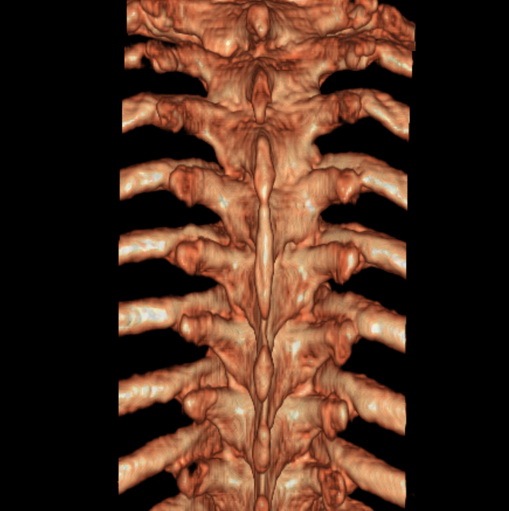

标题: CT25377:脊柱有无压缩骨折?

女、73、胸痛、胸闷3个月,无明显外伤病史,x线疑t4、t7陈旧压缩骨折,ct未经明显骨折,请问结论如何报?

老年女性病人,骨质稀疏,有些驼背,t4明显变扁,t7略变扁,椎体边缘无中断,骨小梁排列正常,无嵌插所致致密线。结合无明显外伤史,考虑老年骨质稀疏,慢性压缩改变,正如老年人骨质稀疏椎体呈双凹改变一样。我考虑报:老年骨质稀疏,t4、t7楔形变,脊柱曲度改变(驼背).敬请大家指教。